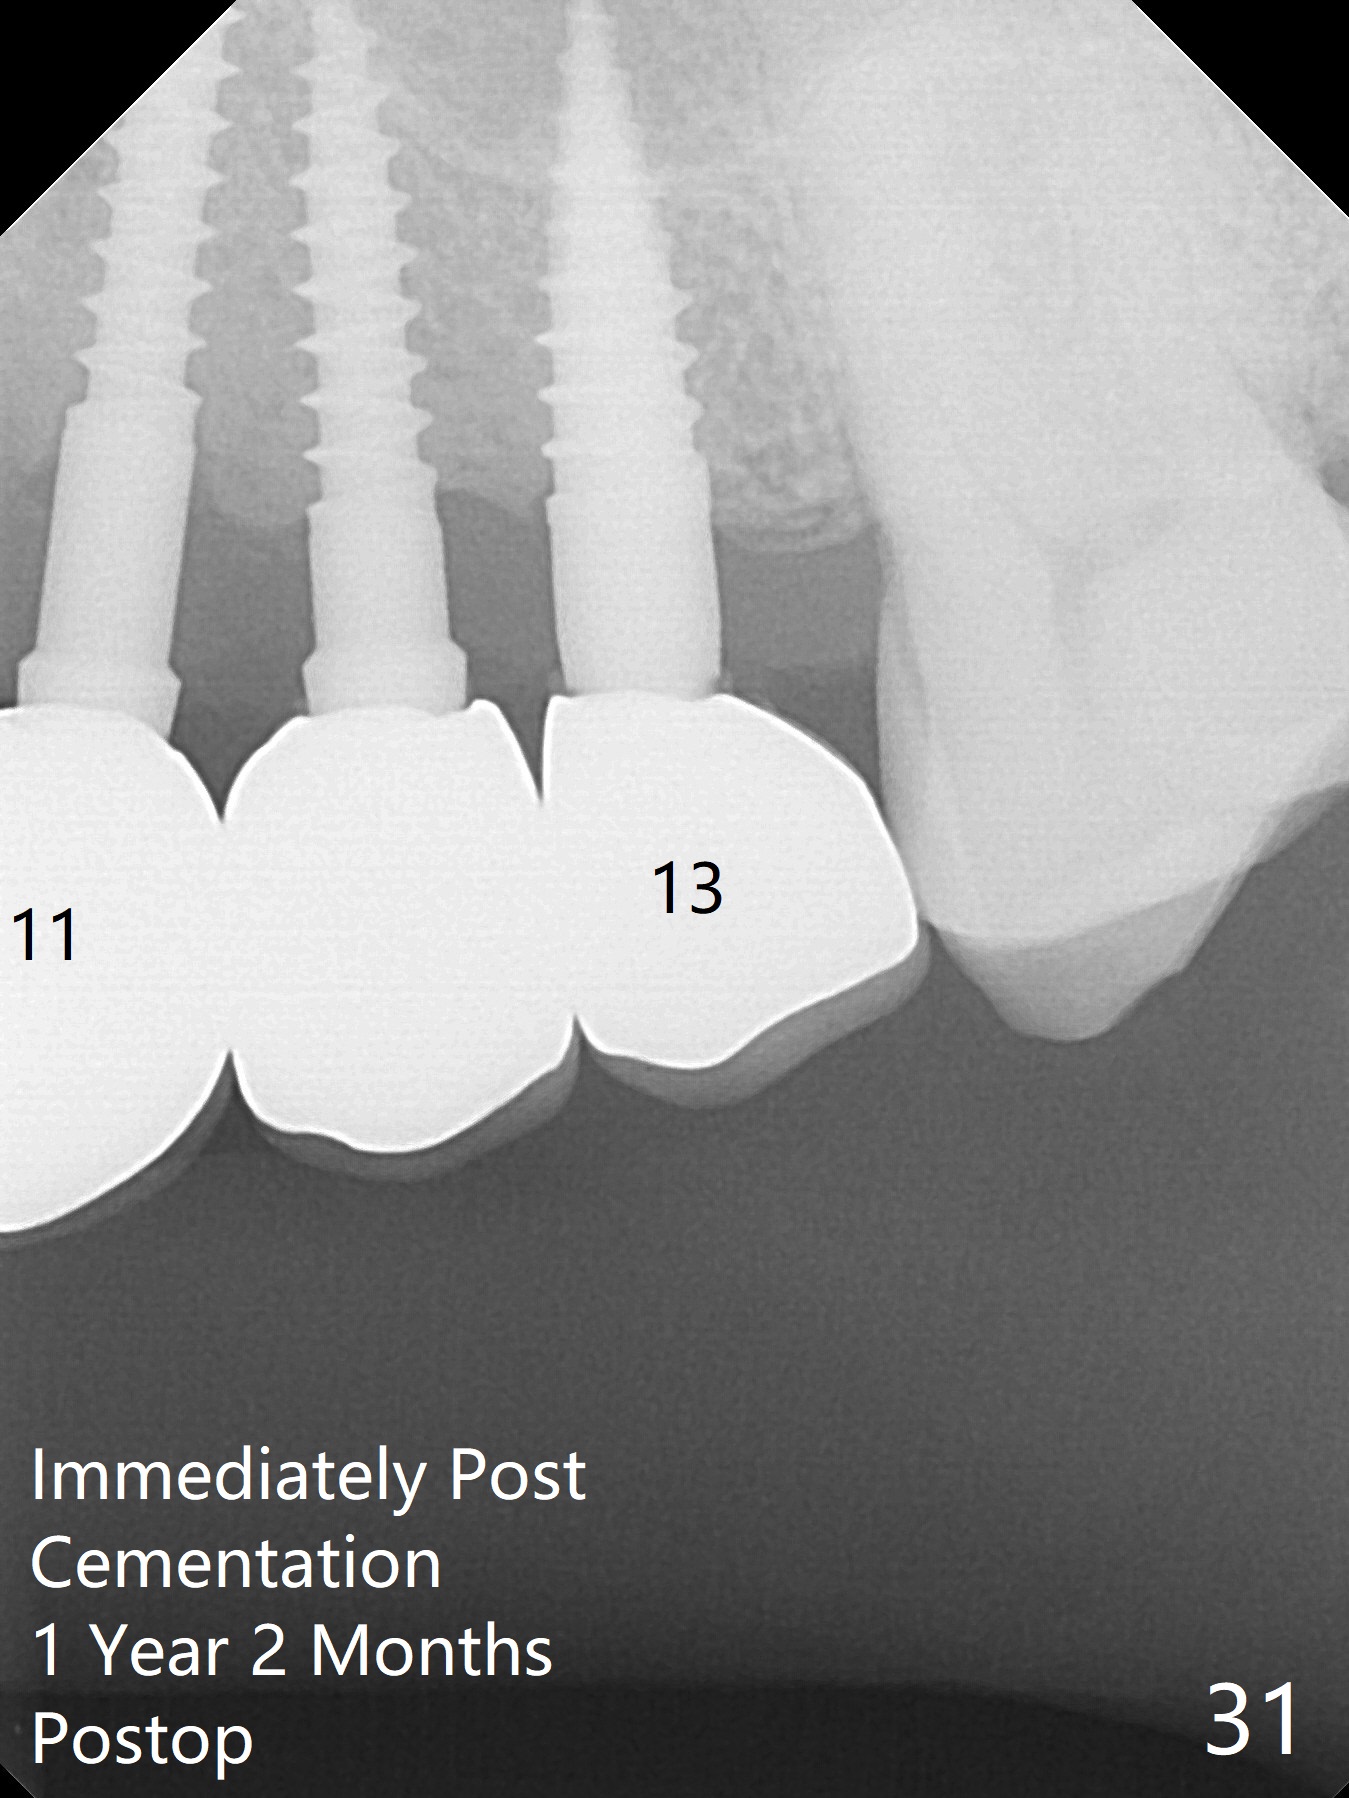

The gingiva remains healthy with use of water pik at #8-10 (4 months post cementation) and at #11-13 (immediately post cementation (1 year 2 months postop, Fig.27,28), while bone loss is minimal (Fig.29-31, although the crowns at #8 and 9 received trauma from child head immediately post cementation with tenderness for 1-2 months). The patient is pleased with convenience of the fixed restoration.